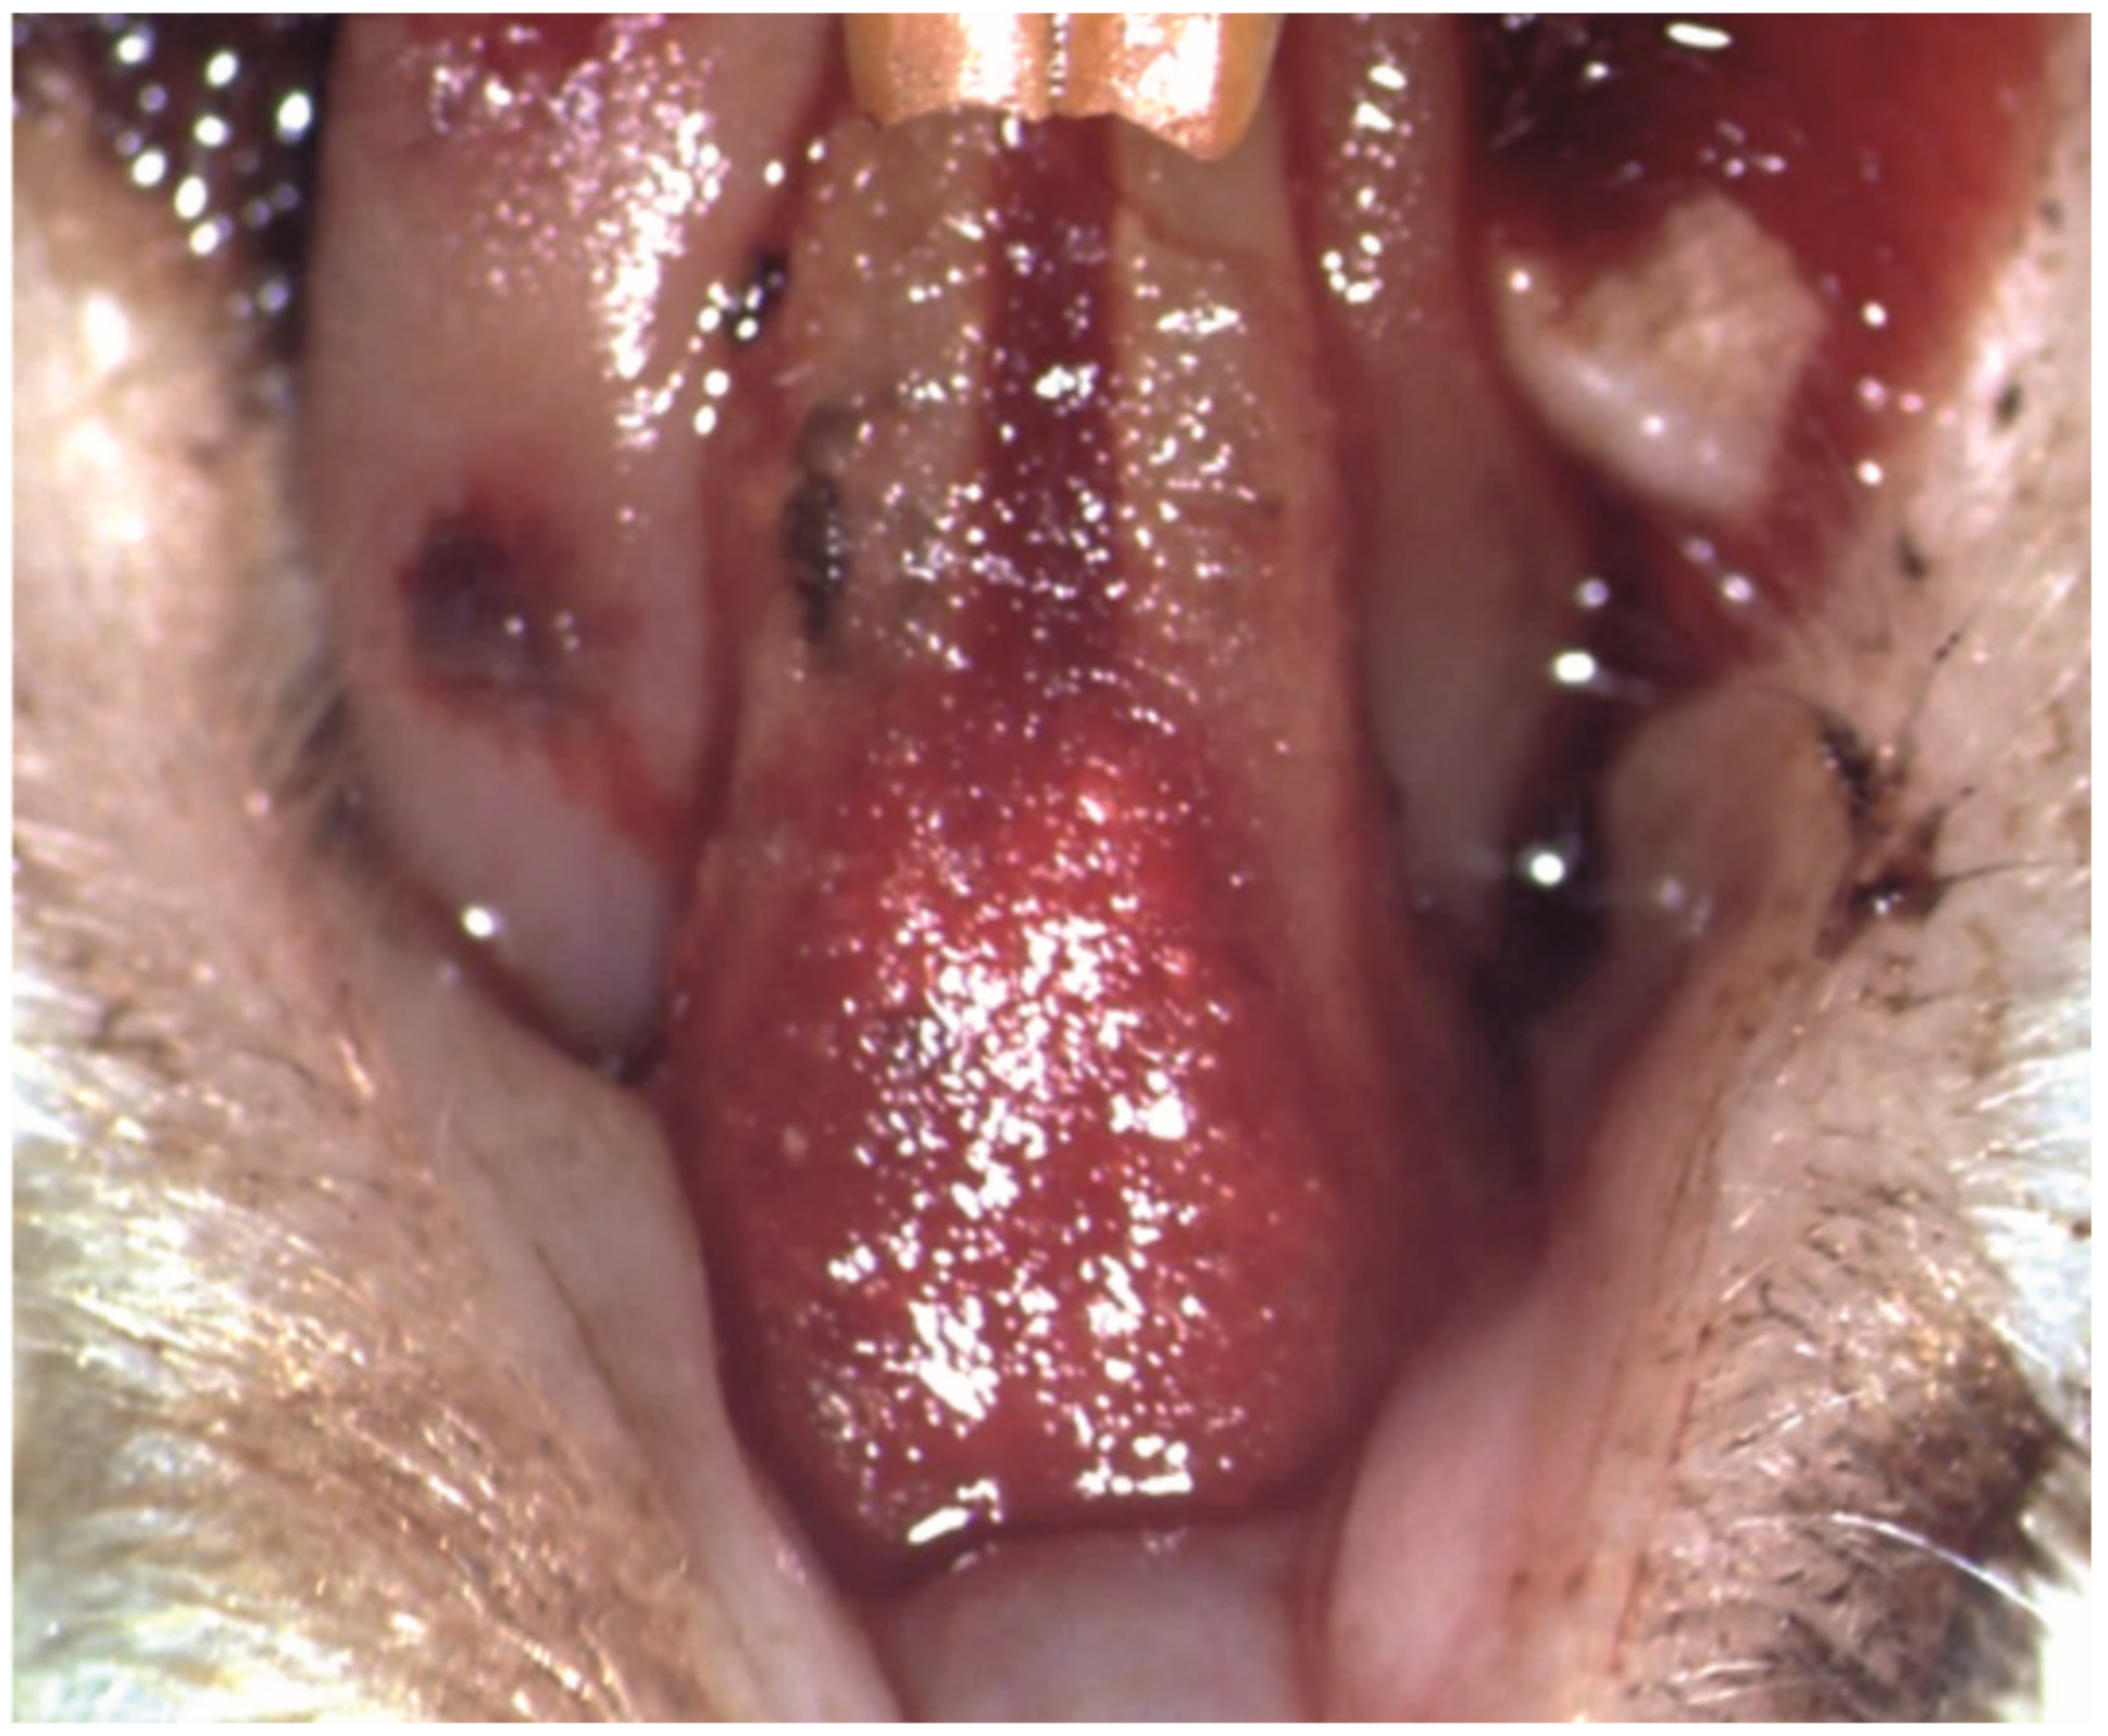

The ligatures were successfully applied to all the subjects in groups PC, T1 and T2 (Figure 3A), and remained in place until removal in the phase 2, 14 days later (Figure 3B).

Figure 3. Clinical aspect of the ligatures on the lower incisors of a subject: (A) at the moment of application (25× magnification); (B) after 14 days, food debris could be found during the ligature removal (white arrow) (10× magnification).